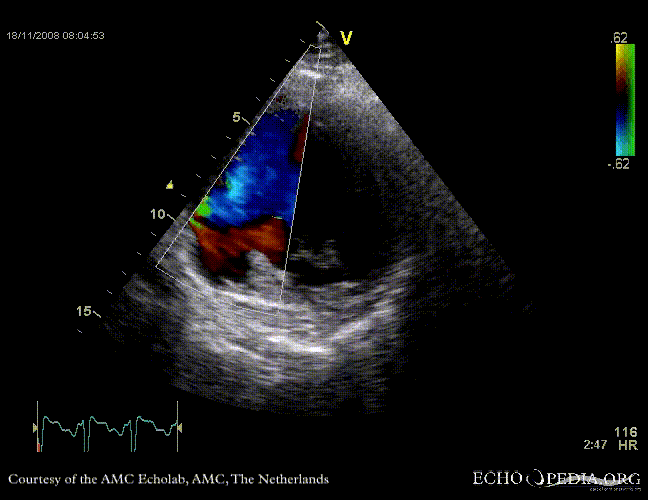

Rupture of the ventricular septum

VSR 1